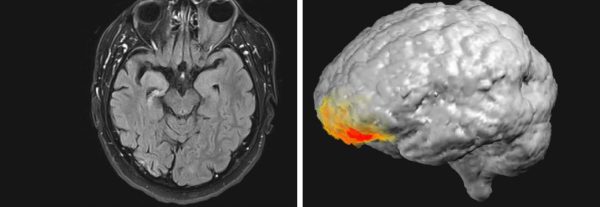

Como podemos ver, do lado esquerdo temos o cérebro do paciente, e do lado direito temos a localização da atividade neural durante a experiência religiosa.

Mesmo depois de tirar os eletrodos, o paciente ficou andando pelo hospital, dizendo a quem quer que ele encontrasse que “Deus me mandou para você.” Mas o mais impressionante foi o registro da atividade cerebral do homem, onde o relatório aponta um pico de atividade na banda gama baixa (30-40 Hz) no córtex pré-frontal esquerdo no momento exato da experiência sobrenatural, o lado oposto do cérebro onde as convulsões se originam. O diagnóstico era que o paciente estava experimentando “delírios religiosos de revelação e zelo missionário no contexto da psicose pós-ictal” (PPI).